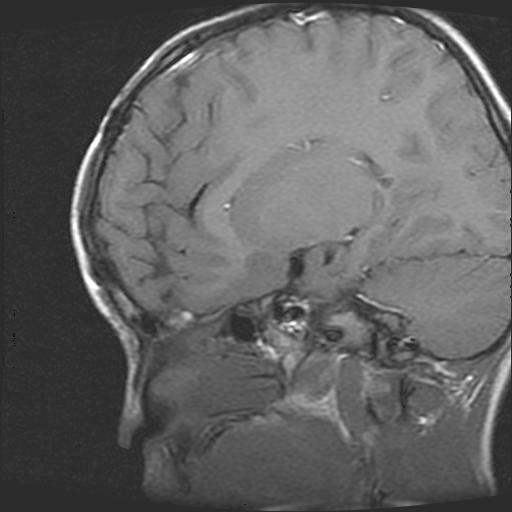

6岁小儿,左侧视神经瘤术后。现左侧视力减退。